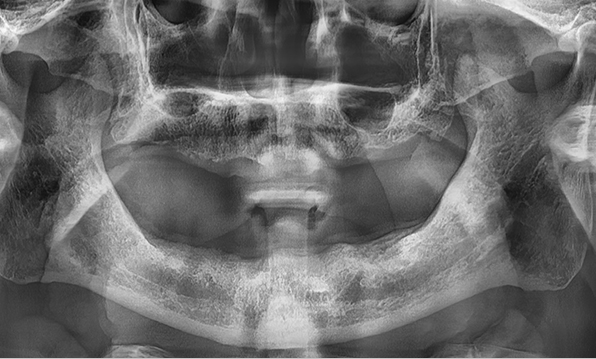

Before & After

Case 01

Before After